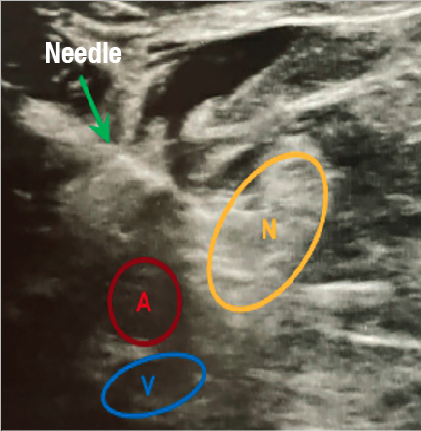

Ultrasound guidance and nerve stimulation techniques are the main techniques employed to identify the sciatic nerve during popliteal blocks. These techniques may be used in isolation, or in combination to confirm injection placement within the popliteal fossa. Nerve stimulation involves insertion of a needle that connects to a stimulator delivering electrical current in a pulsating fashion. As the needle advances and approaches the nerve, one will observe a motor response of the foot. The operator will then decrease the electrical current to approximately 0.5mA while still maintaining motor function. This lower current ensures proximity to the nerve, which serves to target the anesthetic to the epineural location.7

Ultrasound-guided popliteal blocks offer direct visualization of the nerve, unlike the nerve stimulation technique. Ultrasound can help confirm anatomic variation of the nerve course, as well as provide visualization of the anesthetic during injection and diffusion adjacent to the nerve. Evidence supports ultrasound guidance and nerve stimulation as successful when used in isolation, or in combination.8-10 Previous randomized controlled trials reported better success rates of popliteal blocks when performed by ultrasound guidance compared to nerve stimulation, while others have shown no difference in block performance or complication rates.8-10

Some feel ultrasound guidance is advantageous over nerve stimulation because of the ability to visualize the nerve rather than having to use palpation, landmarks, and continual testing of motor response to identify the correct anatomic location.11 Danelli and colleagues observed that ultrasound guided techniques may be superior to nerve stimulation for popliteal sciatic nerve blocks.11 They observed ultrasound guidance to lead to more successful analgesia/anesthesia with less procedural pain and requiring less time to perform compared to the nerve stimulation technique. Technique variation, anatomic variants, and physician experience are all variables that continue to influence outcomes of each nerve block technique.11